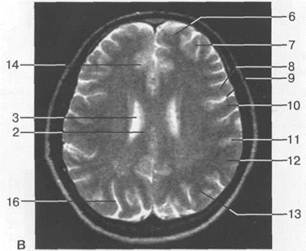

Рис. 1.13. Уровень нижних отделов боковых

желудочков: а — аксиальный срез КТ после

контрастирования; б — аксиальный срез МРТ

(Т1-ВИ); в — аксиальный срез МРТ (Т2-ВИ).

1 — серп; 2 — верхняя лобная извилина; 3 — средняя лобная извилина; 4 — передняя мозговая артерия; 5 — латеральная щель; 6 — таламус; 7 — треугольник бокового желудочка; 8 — червь; 9 — поясная бороз­да; 10 — нижняя лобная извилина; 11 — верхняя височная извилина; 12 — шишковидная железа; 13 — цистерна четверохолмия; 14 — прямой синус; 15—лобный рог; 16 —головка хвостатого ядра; 17 —перед­ний отдел латеральной щели; 18 — внутренняя капсула; 19 — боковой отдел латеральной щели; 20 — ва­лик мозолистого тела; 21 — теменно-затылочная борозда; 22 — шпорная борозда; 23 — поясная извили­на; 24 — предцентральная извилина; 25 — центральная борозда; 26 — постцентральная извилина; 27— средняя височная извилина; 28 — затылочная доля; 29 — внутренняя вена мозга; 30 — затылочный рог; 31 — поперечная височная извилина (извилина Гешле); 32 — наружная затылочная извилина; 33 — шпор­ная извилина; 34 — мозолистое тело.

слеживаются передние рога боковых желудочков, разделенные прозрачной перегородкой. В норме дистальные отделы передних рогов остроконечные. Это весьма важно в практичес­ком отношении, так как развитие гидроцефалии ведет в первую очередь к баллонообразной деформации передних рогов боковых желудочков.

По латеральному контуру каждого рога отчетливо дифференцируется более плотное ана­томическое образование — головка хвостатого ядра, латеральнее и чуть дорсальнее которой проходит линейной формы переднее бедро внутренней капсулы, идущее косо. Приближаясь к III желудочку, внутренняя капсула меняет направление хода, образуя при этом колено, и идет латерально кзади. Эта часть внутренней капсулы называется задним бедром. Оно раз­деляет зрительный бугор и лентикулярные ядра, которые имеют треугольную форму. Поза­ди зрительного бугра идет ретроталамическая цистерна, ориентированная во фронтальной плоскости.

Центральное место в этом регионе занимает ретропинеальная цистерна с шишковидной железой, также относящаяся к срединным структурам головного мозга и располагающаяся по­зади III желудочка (рис. 1.13). Она имеет округлую форму, размеры не превышают 10 мм в ди­аметре. В передних отделах прослеживаются поводки, идущие в сагиттальной плоскости. Именно с них начинается обызвествление шишковидной железы. Латеральные отделы голов­ного мозга на этом уровне представлены островком височной доли, который легко распозна­ется благодаря обилию субарахноидальных пространств, отражающих короткие извитые бо-